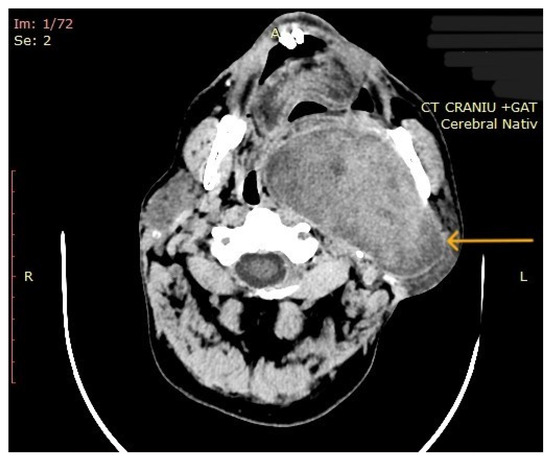

3.2. Imaging Aspects

| 10 | Left parapharyngeal region with maxillary and intracranial extension | Discomfort in breathing, chewing, swallowing, phonation, sleeping, regional pain, fatigue | 5 years | 10 cm | Benign tumor of soft tissue |